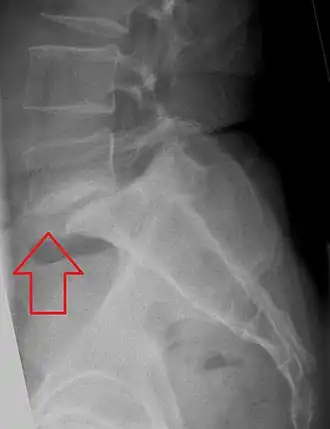

Imagerie

Le cliché de profil montre et quantifie le glissement antérieur du corps vertébral, mais le bord postérieur du sacrum peut être difficile à percevoir. Les 3/4 montrent le plus souvent la lyse isthmique lorsqu’elle existe. Compte tenu de la fréquence des spondylolisthésis de grade I bien tolérés, le bilan complémentaire recherche d’autres pathologies à même d’expliquer une symptomatologie lombaire ou radiculaire chez un adulte jeune [44], en particulier à un autre niveau. Enfin dans une perspective chirurgicale, on recherche l’état d’hydratation du disque sus-jacent, le volume du tissu de pseudarthrose, la morphologie des pédicules et la présence de “ crochets ” pédiculaires nécessitant résection.